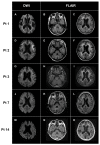

Neuronal intranuclear inclusion disease (NIID) is a neurodegenerative disorder that is caused by the abnormal expansion of non-coding trinucleotide GGC repeats in NOTCH2NLC. NIID is clinically characterized by a broad spectrum of clinical presentations. To date, the relationship between expanded repeat lengths and clinical phenotype in patients with NIID remains unclear. Thus, we aimed to clarify the genetic and clinical spectrum and their association in patients with NIID. For this purpose, we genetically analyzed Japanese patients with adult-onset NIID with characteristic clinical and neuroimaging findings. Trinucleotide repeat expansions of NOTCH2NLC were examined by repeat-primed and amplicon-length PCR. In addition, long-read sequencing was performed to determine repeat size and sequence. The expanded GGC repeats ranging from 94 to 361 in NOTCH2NLC were found in all 15 patients. Two patients carried biallelic repeat expansions. There were marked heterogenous clinical and imaging features in NIID patients. Patients presenting with cerebellar ataxia or urinary dysfunction had a significantly larger GGC repeat size than those without. This significant association disappeared when these parameters were compared with the total trinucleotide repeat number. ARWMC score was significantly higher in patients who had a non-glycine-type trinucleotide interruption within expanded poly-glycine motifs than in those with a pure poly-glycine expansion. These results suggested that the repeat length and sequence in NOTCH2NLC may partly modify some clinical and imaging features of NIID.